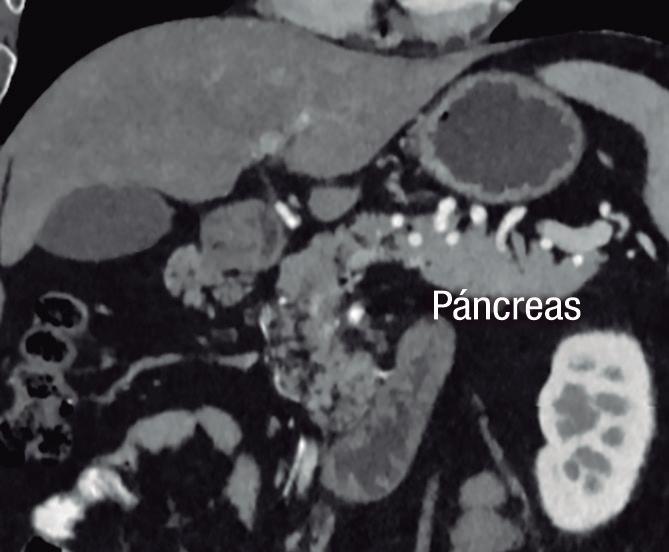

Se refiere a la presencia de tejido pancreático fuera de su ubicación normal y sin conexión con el parénquima glandular principal. Su localización más frecuente es en el tracto gastrointestinal, con mayor prevalencia en el estómago y duodeno, aunque también puede estar presente en otros sitios como el mesenterio, epiplones e incluso en el hígado (Figuras 11 y 12). La hipótesis más aceptada es que corresponde a la proliferación de tejido pancreático a partir de restos celulares de los brotes embriológicos.

A) Tomografía computada con contraste, plano axial. Presencia de tejido ectópico pancreático en topografía del epiplón menor. B) Tomografía computada con contraste, plano axial, corte más caudal. Sector de reemplazo graso difuso en el interior de la heterotopía pancreática (flecha). C) Tomografía computada con contraste, plano coronal. Las flechas señalan el páncreas ectópico en topografía del epiplón menor, en contacto con el estómago (cabeza de flecha).

A) Tomografía computada con contraste, plano axial. Flechas: Páncreas anular. Cabeza de flecha: Páncreas ectópico en la 1° porción del duodeno. B) Tomografía computada con contraste, plano coronal. Flecha: Páncreas anular. Cabeza de flecha: Páncreas ectópico en la 1° porción del duodeno.

Si bien suele ser asintomática la heterotopía pancreática está formada por tejido funcionante que por lo tanto es susceptible a sufrir las mismas patologías que el páncreas normotópico, pudiendo desarrollar pancreatitis e incluso dar lugar a tumores exocrinos (adenocarcinoma) y endocrinos.20